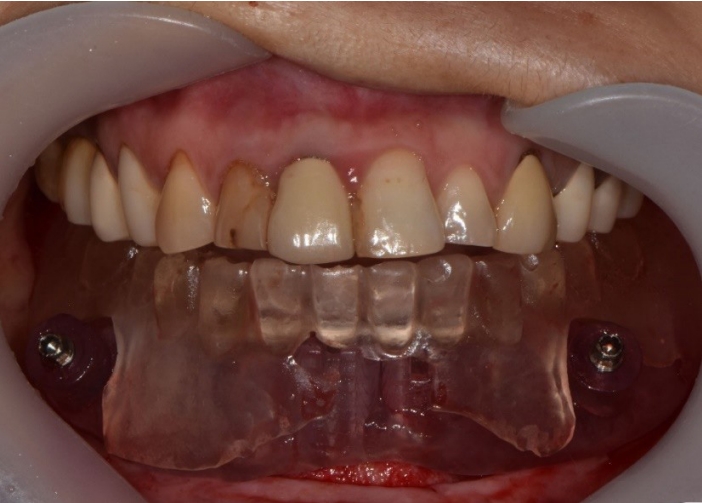

본 증례는 44세 여환으로, 하악 의치가 계속 탈락하여 재제작을 원한다는 주소로 내원하였다. 상악은 고정성 수복물, 그리고 하악은 총의치를 착용 중이었고 하악 양측 구치부의 심한 골 흡수로 인해 유지력 소실로 불편감을 호소하였다. 3개월 전 하악 양측 견치를 발거한 이후로 하악 국소의치를 총의치로 전환하였고, 총의치는 구치부의 심한 교합면 마모와 의치의 후방부가 후구치 삼각 융기를 피개하지 않는 형태였다. 전신 병력으로는 지적장애 및 골관절염으로 약 2개월 간 약물 복용 중이었다. 상악 우측 제1대구치와 제2대구치, 제1소구치 그리고 제2소구치는 우식이 진행된 상태였고, 우측 제2소구치와 우측 제1대구치는 근관치료가 완료된 후 수복되지 않은 상태였다. 상악 좌측 제1소구치와 제2소구치, 그리고 제1대구치 수복물 하방으로 이차 우식이 진행된 상태였고, 전체적으로 교합평면이 균일하지 않은 형태였다(Figs. 1-3).

Fig. 1.

Atrophy of mandibular posterior bone is examined by pre-operative intraoral photograph. A. Maxillary occlusal view. B. Frontal view. C. Mandibular occlusal view.